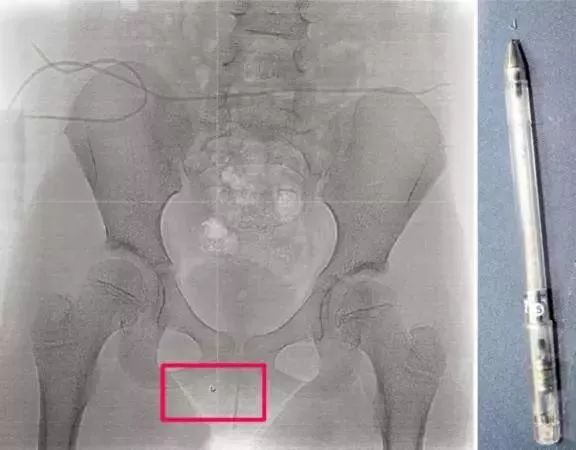

一名九岁的男孩,在同桌的椅子上放了一支油性笔,十几厘米长,90度垂直,笔尖朝上。

女孩毫无防范地坐下,瞬间,笔尖戳破右侧大腿,顺力直插会阴部,一声凄厉的惨叫划破教室……

一支十几厘米长的油性笔戳破大腿

笔尖戳破会阴部并滞留体内